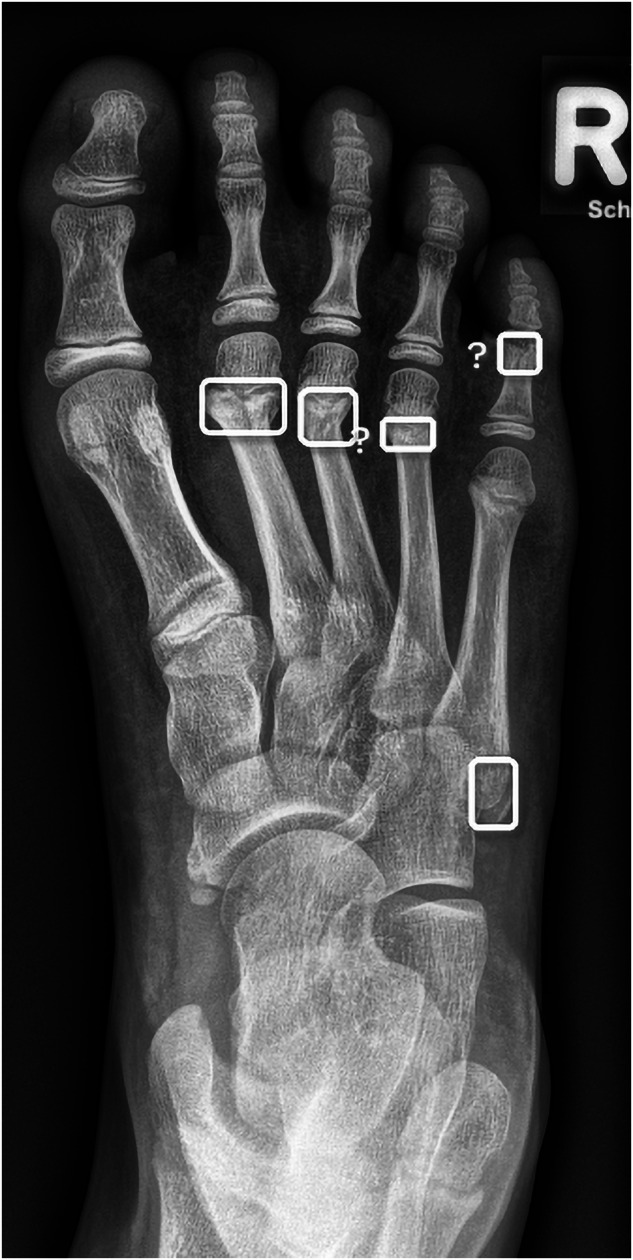

Objectives: This study aimed to evaluate the performance of an artificial intelligence (AI)-based software for fracture detection in pediatric patients within a real-life clinical setting. Specifically, it sought to assess (1) the stand-alone AI performance in real-life cohort and in selected set of medicolegal relevant fractures and (2) its influence on the diagnostic performance of inexperienced emergency room physicians.

Materials and methods: The retrospective study involved 1672 radiographs of children under 18 years, obtained consecutively (real-life cohort) and selective (medicolegal cohort) in a tertiary pediatric emergency department. On these images, the stand-alone performance of a commercially available, deep learning-based software was determined. Additionally, three pediatric residents independently reviewed the radiographs before and after AI assistance, and the impact on their diagnostic accuracy was assessed.

Results: In our cohort (median age 10.9 years, 59% male), the AI demonstrated a sensitivity of 92%, specificity of 83%, and accuracy of 87%. For medicolegally relevant fractures, the AI achieved a sensitivity of 100% for proximal tibia fractures, but only 68% for radial condyle fractures. AI assistance improved the residents' patient-wise sensitivity from 84 to 87%, specificity from 91 to 92%, and diagnostic accuracy from 88 to 90%. In 2% of cases, the readers, with the assistance of AI, erroneously discarded their correct diagnosis.

Key points: Question Does an artificial intelligence-based software for fracture detection influence inexperienced physicians in a real-life pediatric trauma population? Findings Addition of a well-performing artificial intelligence-based software led to a limited increase in diagnostic accuracy of inexperienced human readers. Clinical relevance Diagnosing fractures in children is especially challenging for less experienced physicians. High-performing artificial intelligence-based software as a "second set of eyes," enhances diagnostic accuracy in a common pediatric emergency room setting.